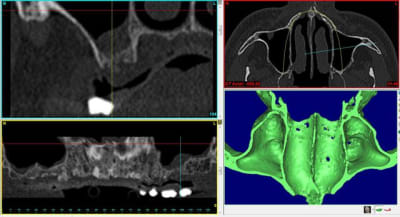

voici 4 scanners montrant la différence de résultat obtenu après un sinus lift.

1 gauche : avant

2 droite : avant

3 droite : après

4 gauche : après

notez surtout qu'à gauche et à droite la consistance est vraiment différente.